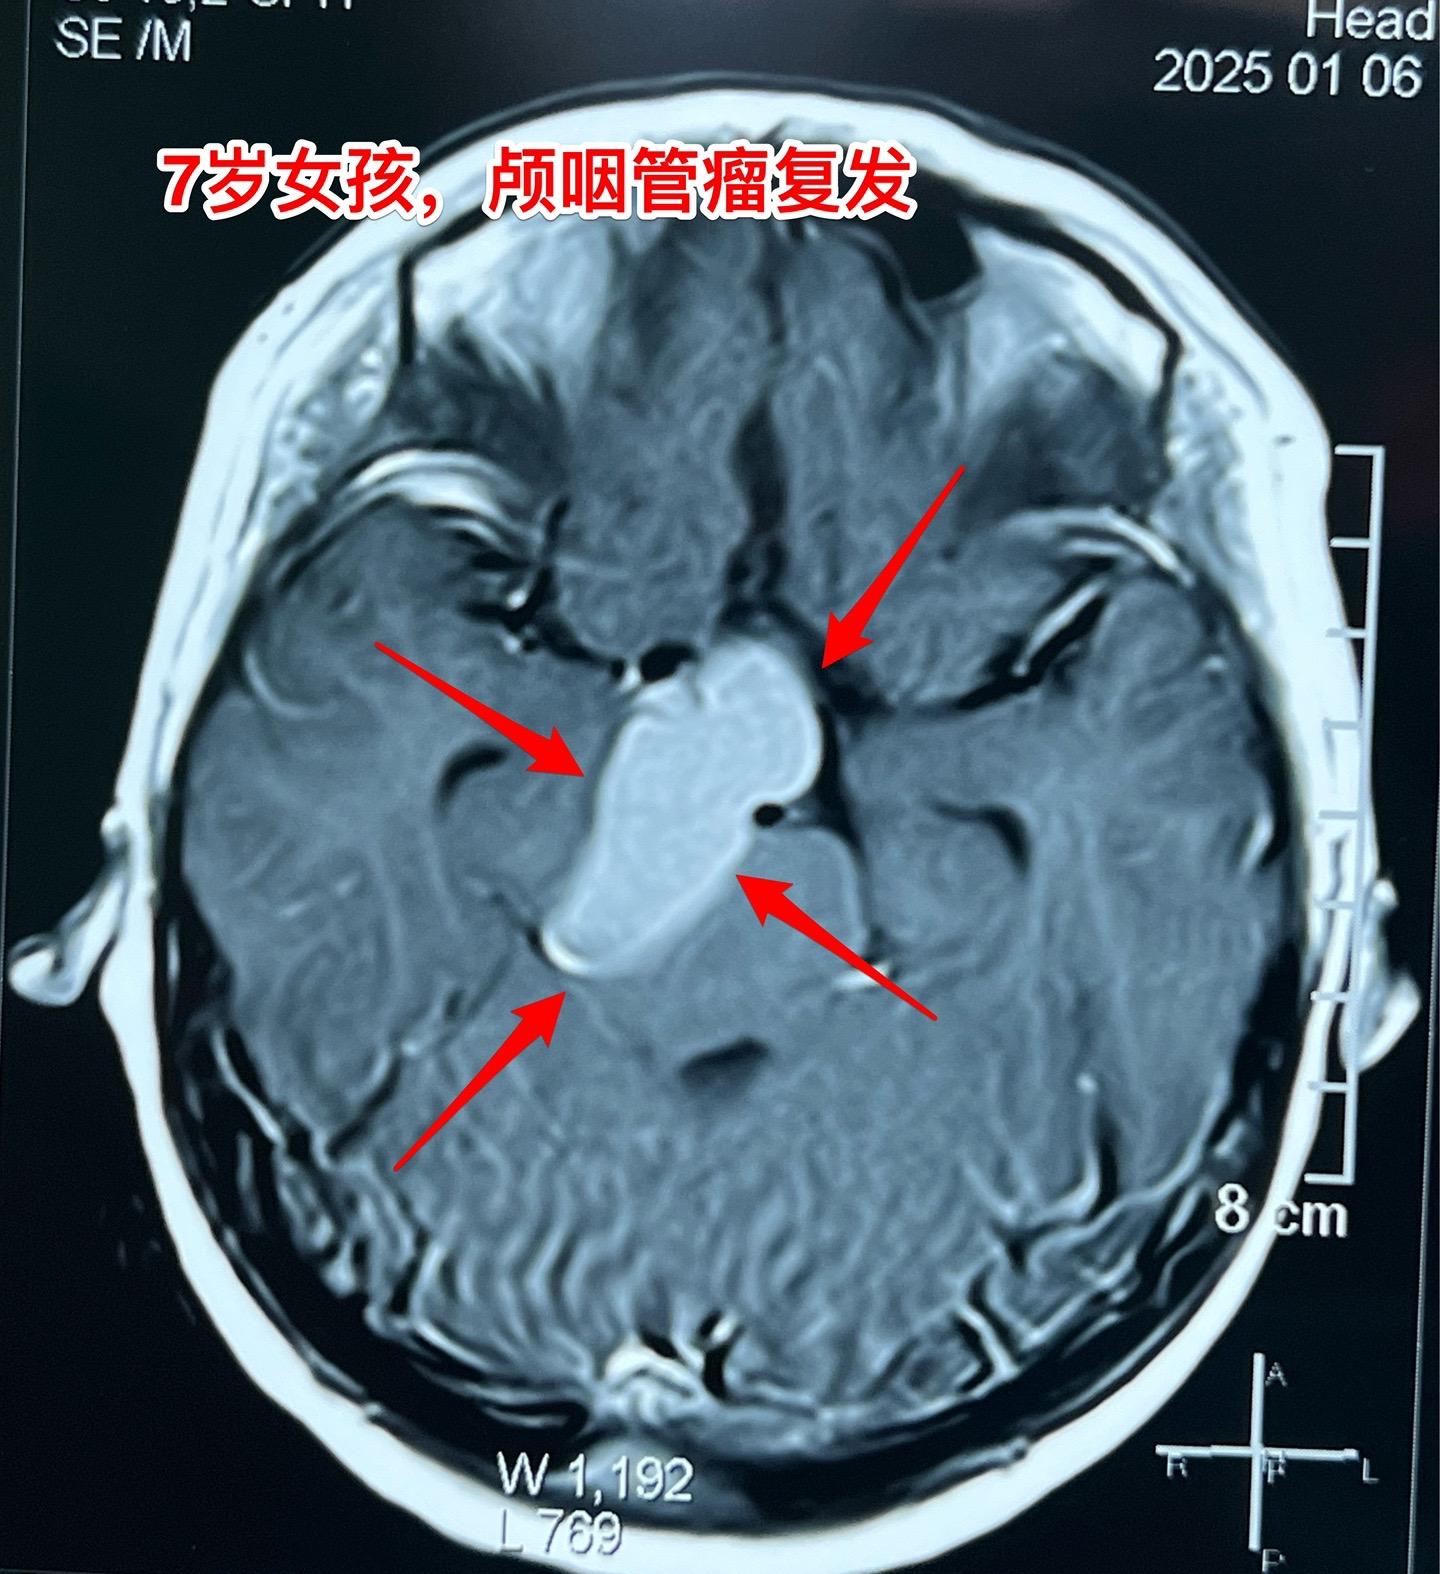

颅咽管瘤复发,看起来是一个瘤其实有三个。7岁女孩子,颅咽管瘤复发。从CT和磁共振来看,是一个大的囊性肿瘤,体积很大了,肿瘤向后颅窝生长,手术切除的难度还是比较大的。 2025年1月10日作手术过程中发现的情况比预想的还要复杂得多。除了这个大的囊性肿瘤之外还发现了两个孤立肿瘤。 这样的情况在我们科并不罕见,经常发现复发的颅咽管瘤病人脑部不止是一个瘤,有的时候有超过10个孤立的肿瘤。这种情况就要考验医生的技术和意志力了。当然,在我们科,总是争取把看见的瘤完全切除。